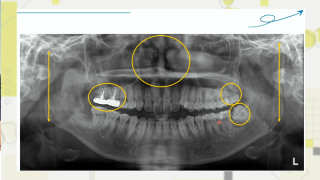

ドクターのための現代矯正学4 補綴×インビザラインによる治療効果と利益の最大化計画(世界初の非抜歯セットバック症例レポート動画セット)

世界初の矯正治療を成功させたドクターが語るGPだからできる全顎的治療とは?